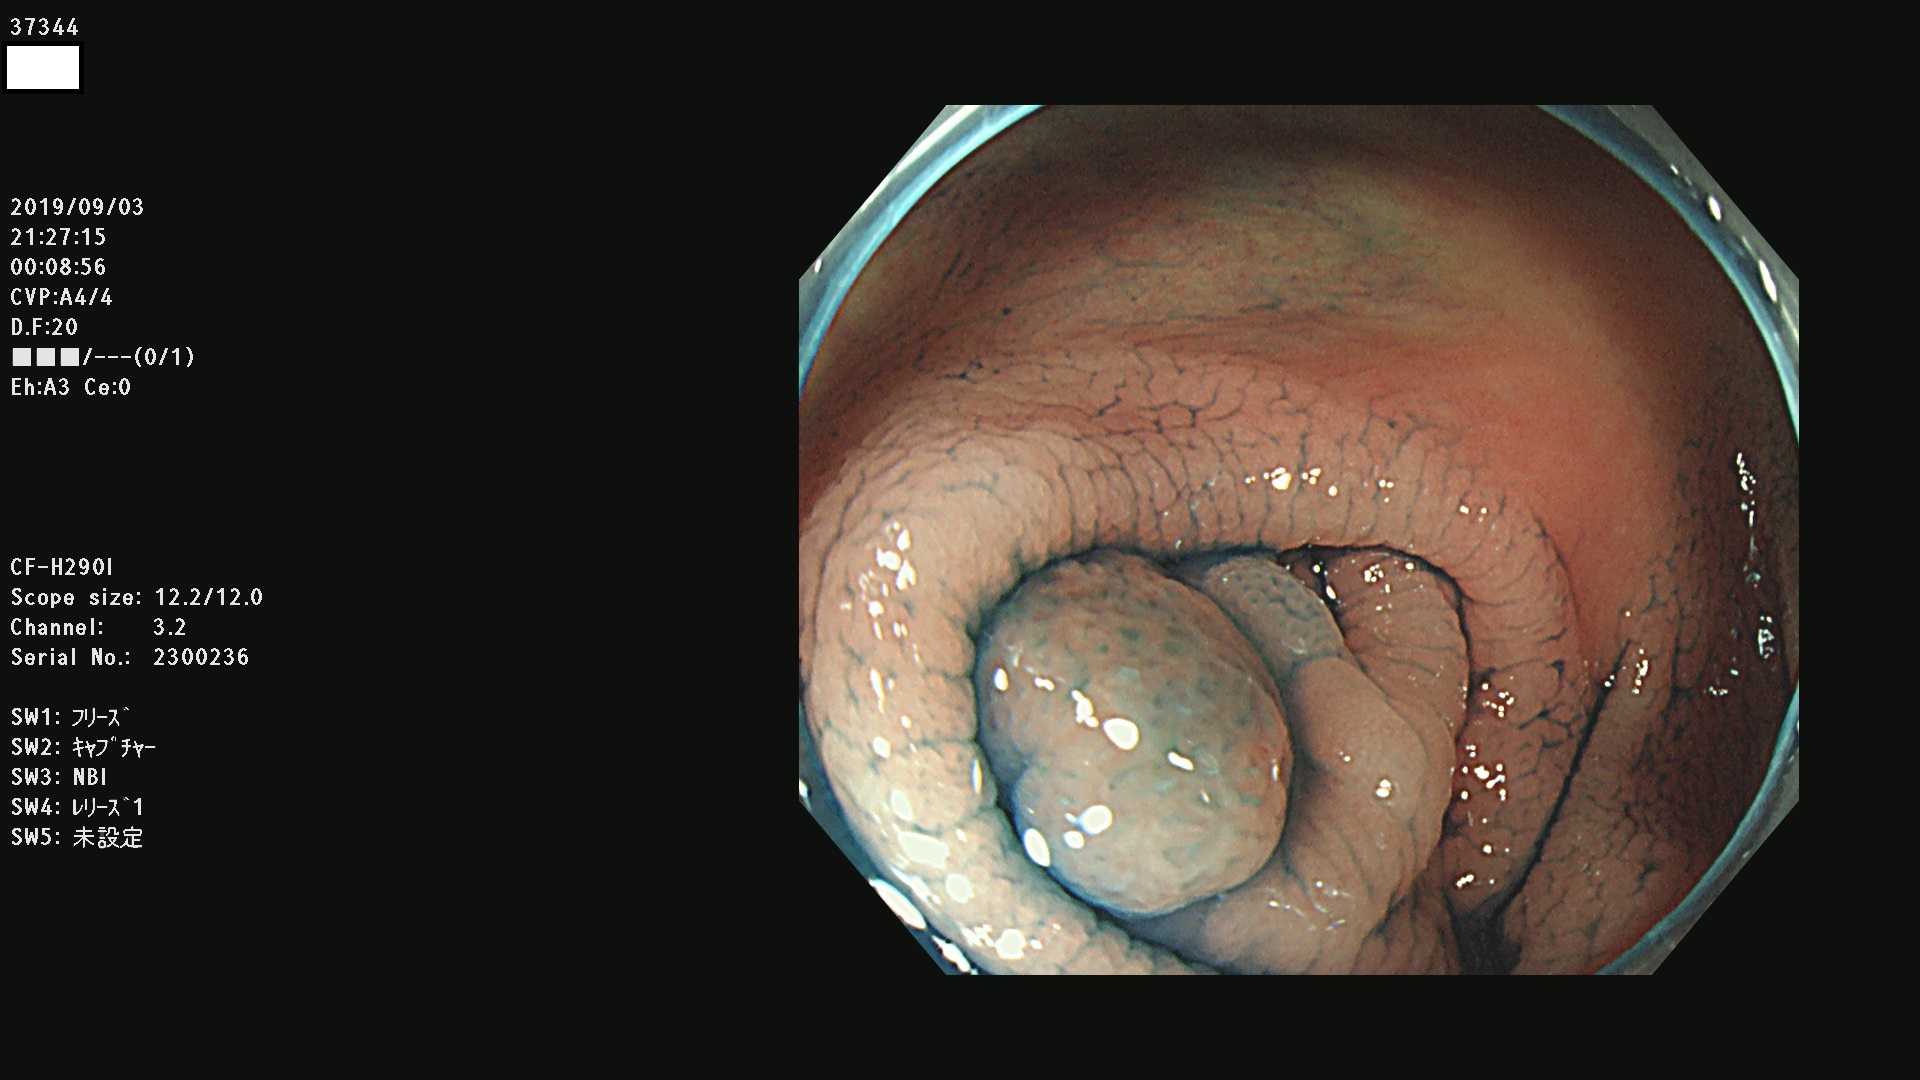

37300(SSAPのみ) 37301 37303 37304 37306 37307 37308 37309 37312 37313 37315(SSAPのみ) 37316 37317(SSAPのみ) 37319 37321(SSAPのみ) 37322 37323 37324 37325 37326 37328(SSAPのみ) 37329 37330 37331 37332(SSAPのみ) 37333 37334 37336 37337 37338 37340 37342 37343(SSAPのみ) 37344 37345 37346 37347 37348 37352(SSAPのみ) 37353 37354 37355 37356 37358 37360 37361(SSAPのみ) 37362 37363 37366 37367 37369 37370 37371 37372(SSAPのみ) 37375 37376 37377 37380 37381(SSAPのみ) 37382 37383 37384 37385(SSAPのみ) 37386 37387 37388 37389 37390 37392(SSAPのみ) 37393 37394 37395 37396(SSAPのみ) 37397 37398(SSAPのみ) 37399

発見困難で危険性の高い平坦型病変(上記100名より抽出) )